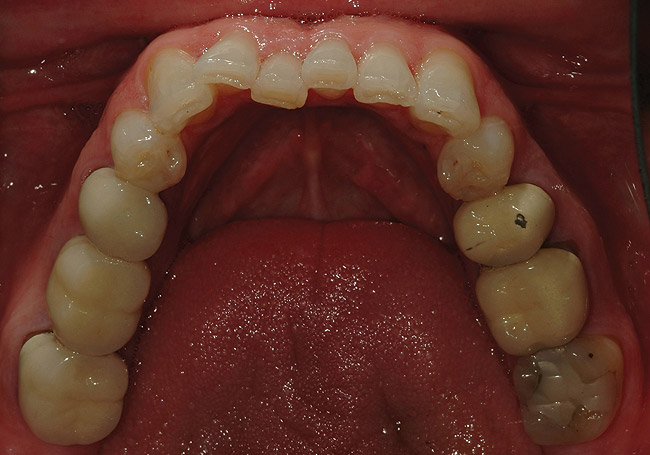

Figure 8  Preoperative view of the upper arch.

Figure 8

Figure 9: Preoperative view of the lower arch.

Figure 9